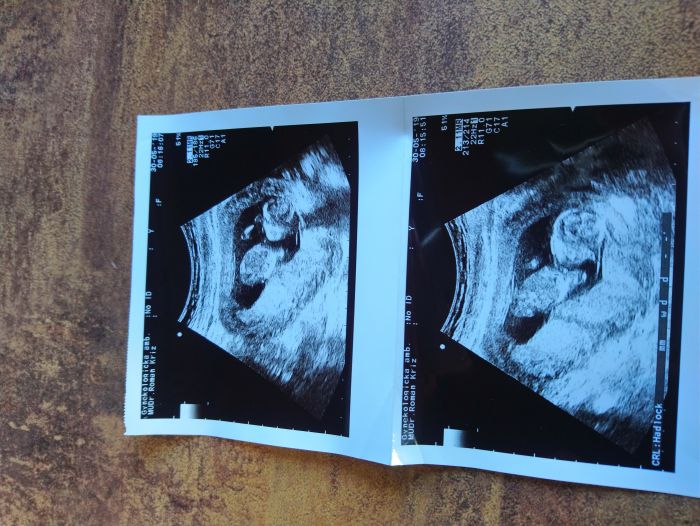

Ahoj holky, tak miminko podle doktora je v pořádku to mám radost a s manželem jsme poprvé slyšeli srdíčko bylo to nádherné a dojemné tak termín porodu mám buď 3.12. nebo 5.12.

Ahoj holky, tak po důkladném čtení všech Vašich příspěvků se k Vám přidávám

momentálně jsem 12+4, první screening za námi (vše je ok). V červnu další kontrola u gynekologa a další kontrola na genetiku. Doktor říkal že prcek je pěkný skokan

pořád se mlel a plácal rukama

jinak termín porodu podle ultrazvuku je 9.12. Hezký den Všem

Ahojky holky, tak mam po screeningu a dopadl moc dobře. Termín porodu podle ultrazvuku mam 13.12. A na 80%čekáme holčičky